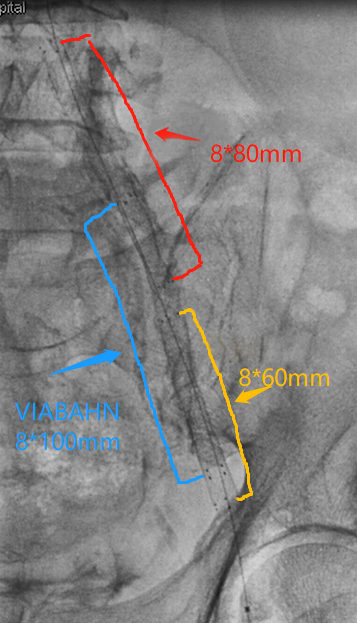

左侧髂总动脉管腔中-重度狭窄,为尽可能减小对左侧髂内动脉的影响,考虑置入Smart自膨式裸支架;左侧髂外动脉闭塞,闭塞段长,且钙化严重,为保证远期通畅率,同时防止血管破裂,考虑置入VIABAHN覆膜支架,为增加径向支撑力,内嵌Smart自膨式裸支架,防止支架管径回缩。

3. 于左侧股浅动脉引出导丝,以血管滑线缝合股总动脉以及股深动脉切口,沿导丝引入8F短鞘,导引3.5mm球囊扩张后,未防止充分预扩导致血管破裂,先行植入支架(依次于髂外植入8*100mm覆膜支架、髂总动脉植入8*80mm支架、髂外动脉腹膜支架内嵌入8*60mm支架),导引8mm球囊进行后扩张,扩张后支架形态如下: